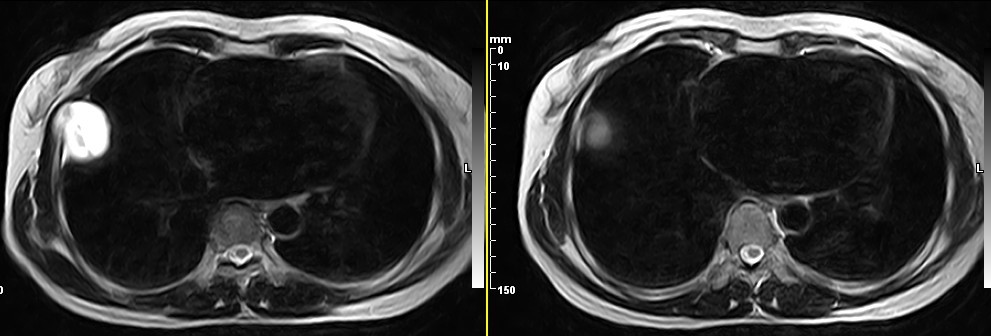

女,49岁。三年前因胸部不适在外院行CT检查诊断报告:右胸壁占位病变,考虑胸膜间皮瘤可能性大。现病人到我院检查了解情况。算是较典型的病变吧?大家看看MR比CT优点在哪里?

病检神经鞘瘤

液性信号符合神经鞘瘤囊变。